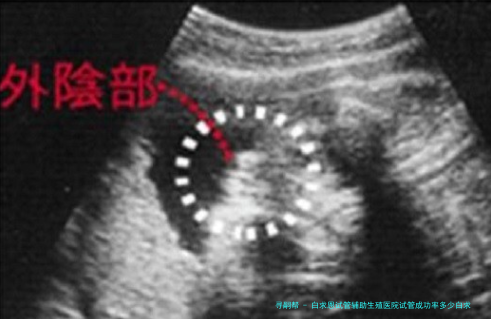

白求恩试管辅助生殖医院做试管婴儿成功率一览

白求恩国际试管辅助生殖医院的试管婴儿成功率相当高。根据此医院的统计数据,他们的成功率保持在40%-50%左右,有些患者身体情况好,成功率会超过60%,这一成功率放置于整个河北试管婴儿医院排名榜中都是无比可观的,至于石家庄市的病患来讲,有须要的可以放心到此医院助孕。